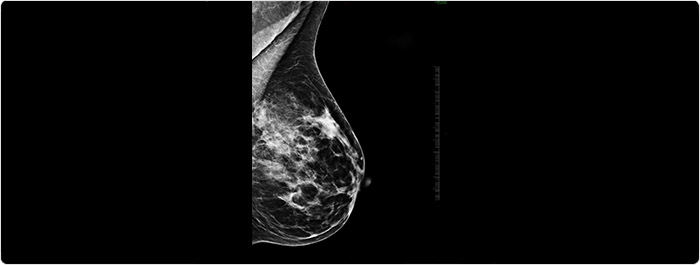

ก้อนในเต้านม (Breast mass หรือ Breast lump) คือ ก้อนเนื้อผิดปกติที่เกิดในเต้านม อาจเกิดเพียงข้างเดียว (ซึ่งพบบ่อยกว่า) หรือเกิดทั้ง2ข้างของเต้านม (ซึ่งพบน้อยกว่า), อาจเกิดเพียงก้อนเดียว (ซึ่งพบบ่อยกว่า), หรือเกิดได้หลายก้อน (ซึ่งพบน้อยกว่ามาก), ก้อนเนื้ออาจมีขนาดเล็กตรวจพบได้จากการตรวจคัดกรองโรคมะเร็งเต้านมด้วยการตรวจภาพรังสีเต้านม/แมมโมแกรม (Mammogram)และ/หรืออัลตราซาวด์เต้านม หรือก้อนเนื้ออาจมีขนาดใหญ่จนสามารถคลำได้โดยตัวผู้ป่วยเองและ/หรือโดยแพทย์

- การตรวจภาพเต้านมด้วยอัลตราซาวด์และ/หรือแมมโมแกรม (การตรวจภาพรังสีเต้านม)

หรือตรวจภาพรังสีเต้านม/แมมโมแกรมและ/หรืออัลตราซาวด์เต้านมเพื่อตรวจคัดกรองโรคมะเร็งเต้านมตั้งแต่ยังไม่มีอาการ โดยเริ่มได้ตั้งแต่อายุ 45-50 ปีขึ้นไปหรือเริ่มตั้งแต่อายุ 40 ปีขึ้นไปเมื่อมีญาติสายตรง (พ่อ แม่ พี่ น้อง ท้องเดียวกัน) เป็นโรคมะเร็งเต้านม ต่อจากนั้นความถี่ของการตรวจภาพรังสีเต้านมขึ้นกับคำแนะนำของแพทย์